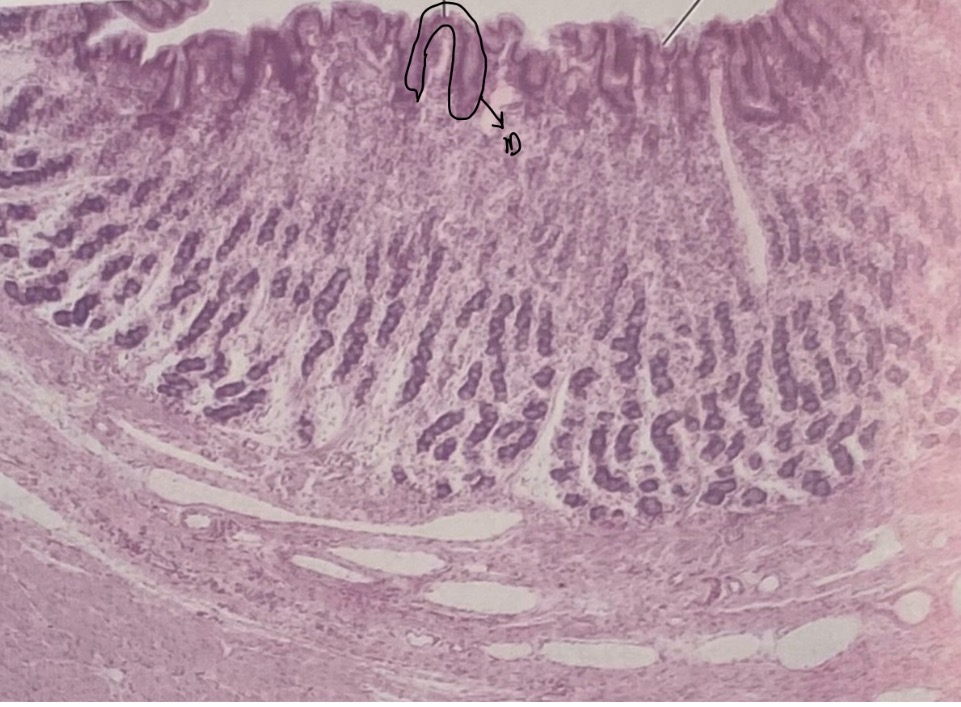

Stomach

Gastric Pit

Mucosal Cells

Parietal Cells

Chief Cells